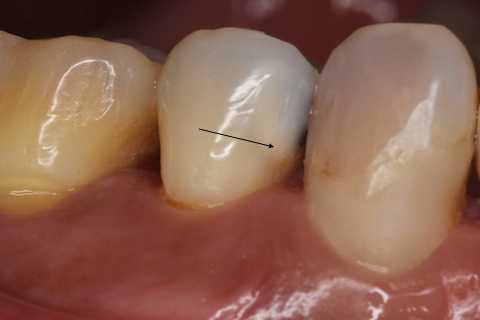

以下は術前の画像だが、5番にも6番にもクラックはあるので、これだけではどちらが沁みているのか特定できない。

5番には術中から気になっていた大きなクラックが認められたので、この部分は裏面の軟化象牙質はエナメル質を壊さないように丁寧に除去してCRで裏打ちし補強を入れた。

術後の画像ではクラックが良く見えると思う。